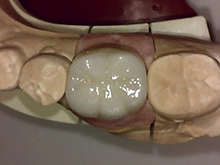

セ ラ ミ ッ ク ク ラ ウ ン

内面には金属を使用し、外面にセラミックを築成するタイプで、従来多くがこの方法で治療されていました。

症 例